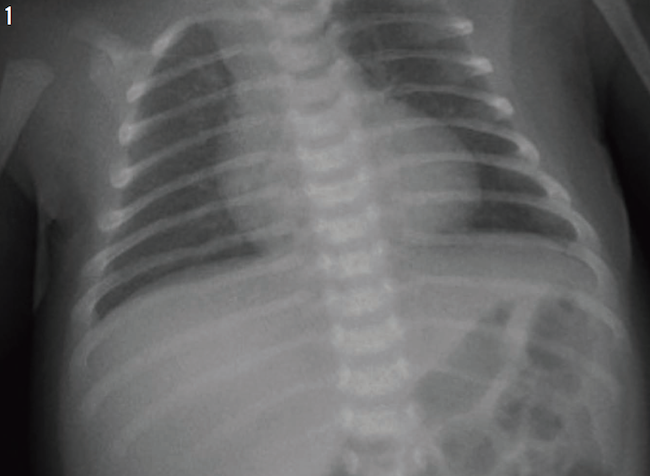

Treatment was started with parenteral clindamycin for presumptive aspiration pneumonia of the right upper lobe. All of her previous radiographs were reviewed (Figures 1-3), and a computed tomography scan of the chest was performed (Figure 4), the latter of which revealed bronchiectasis. Results of a quantitative sweat test were negative for cystic fibrosis, and results of immune function testing were normal.

Figure 1: Chest radiograph of the patient at 1 month of age.